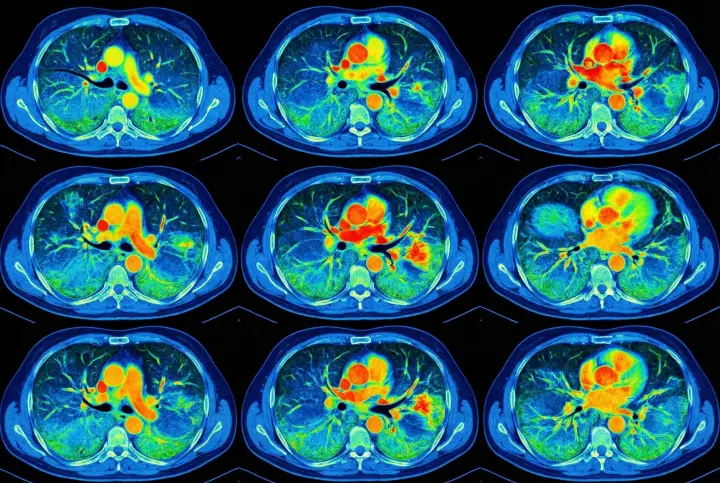

2. COPD progression - the silent suffocator

Untreated lung congestion and airway inflammation often develop into full-scale COPD.

It may begin with mild shortness of breath or an occasional cough-but the damage continues silently.

Before patients realize what's happening, their lung capacity has already declined significantly.

Breathing feels like trying to inhale through a straw.

Most are diagnosed too late-when the condition can only be managed, not reversed.